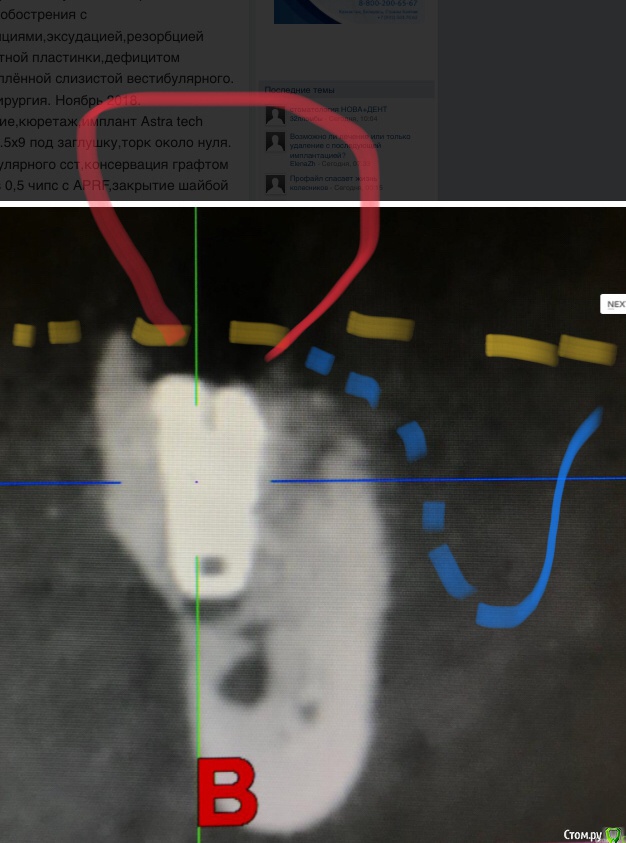

колесников Опубликовано 22 апреля, 2019 Поделиться Опубликовано 22 апреля, 2019 (изменено) И снова профайл спасает жизнь (облегчает жизнь имплантолога)Стандартная ситуация:36 периодонтит в стадии обострения с грануляциями,эксудацией,резорбцией компактной пластинки,дефицитом прикреплённой слизистой вестибулярного. Одна хирургия. Ноябрь 2018. Удаление,кюретаж,имплант Astra tech profile 4.5x9 под заглушку,торк около нуля. Вестибулярного сст,консервация графтом Sureoss 0,5 чипс с APRF,закрытие шайбой по Ноймайеру. Через неделю шайба несостоятельна-удалена. Пациентка созрела на удаление 37го. Выполнена декоронация в связи с отъездом пациентки,далее через 2 недели удаление и имплантация 37го. Промежуточный осмотр в январе. В марте установлены формирователи . Апрель контрольный осмотр. Периотест -5. Направлена на протезирование. Изменено 22 апреля, 2019 пользователем колесников 4 Ссылка на комментарий

колесников Опубликовано 23 апреля, 2019 Автор Поделиться Опубликовано 23 апреля, 2019 Разница от платформы до зенита 3 мм.Ещё раз. Вестибулярно дефект 9мм. Полное отсутсвие прикреплённой слизистой,язычное поднутрение и воспалительный процесс. Чтобы провести олномоментную имплантацию пришлось бы взять короткий имплант,заглубить его на 8мм от зенита,засыпать графтом,перекрыть мембраной,натянуть щеку и ждать-молиться чтобы края не разошлись и все не стухло. А после 2 -3 десневые пластики и глубокая шахта. Господа! Коллеги! Где сроки? Где бюджет? Где прогнозы? Ладно имплант и его глубина, это не так существенно,я вам показал как из ничего за 1 визит получить кератинизированую и прикрепленную слизистую без основания Ссылка на комментарий